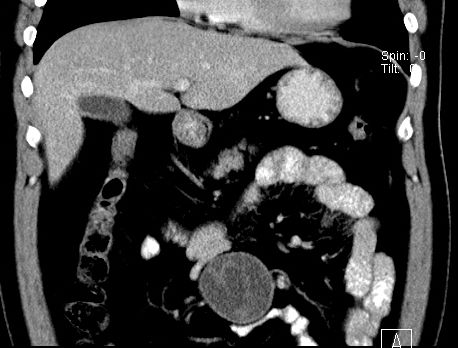

(腹腔)神经鞘瘤

男,48岁,间断性下腹不适1年。

手术探查

:距回盲部28厘米处肠系膜根部可见5*7cm左右包块,质中等硬度,活动度尚可,肝、胆、胰、脾肾未见明显异常。

病理

:(腹腔)

神经鞘瘤

,伴出血、坏死及囊性变,伴淋巴结反应性增生。

免疫组化结果

:sma(-), desmin(-), cd117(-), s-100(+++), nf(-),vimentin(+++).